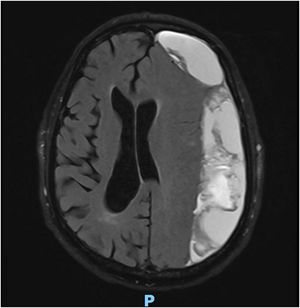

A portable ultrasound system (Chison Q9 with a 7 MHz linear probe) was used to perform a B-mode orbital ultrasound study; optic nerve diameter was 9.6 mm on the right side (Fig. 1) and 6.4 mm on the left.

Optic nerve sheath diameter has been shown to be a useful non-invasive marker of intracranial hypertension; most studies have mainly focused on patients with idiopathic intracranial hypertension, which was subsequently confirmed with lumbar puncture.1 This technique is simple to perform and requires minimal training and theoretical knowledge of ultrasound. It requires an ultrasound system capable of delivering B-mode ultrasound, and a 3-9 MHz multifrequency linear probe. The eye is studied via the transorbital window. The patient is placed in a supine position with the head elevated by 20°-30°. With the patient’s eyes closed, gel is applied to the upper eyelid. The probe is applied with an axial orientation to visualise the optic disc and the retrobulbar region of the optic nerve; at a depth of approximately 3 mm beyond this location, following the trajectory of the optic nerve, the measurement is taken from the external edges of the hyperechogenic rim of the optic nerve, which corresponds to the optic nerve sheath (Fig. 1). The studies evaluated show adequate inter-rater reliability; the normal range has been established at 5.4 ± 0.6 mm.1–3